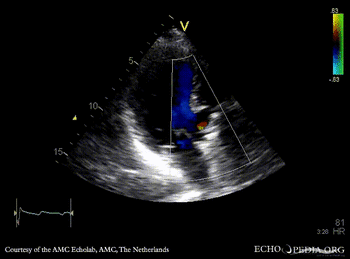

Fistula from ascending aorta to the right ventricle

PLAX: color doppler, fistula from ascending aorta to the right ventricle Continuous-wave signal of flow through fistula